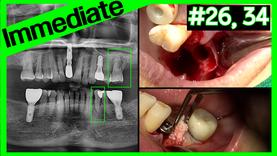

[OSSTEM WORLD MEETING 2026 Bangkok] Immediate Implant Pla...

Osstem Meeting

Views 12